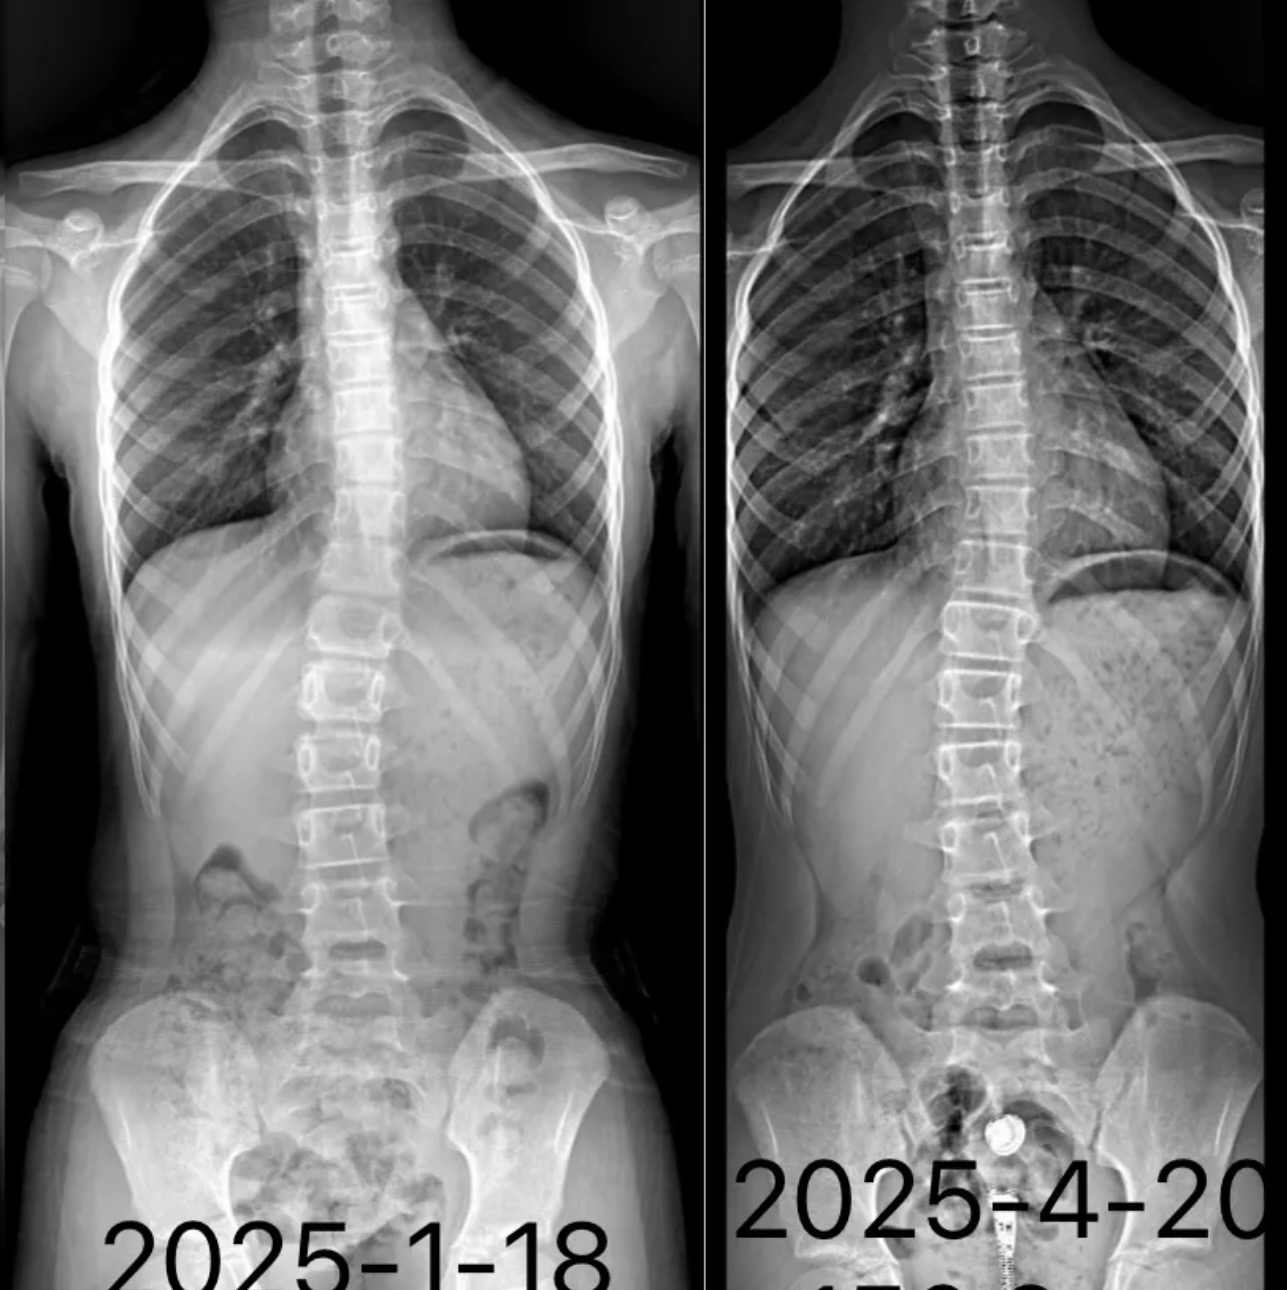

衷德脊柱,我们只关注侧弯保守治疗~

Zhongde Spine, bending no breaking ~